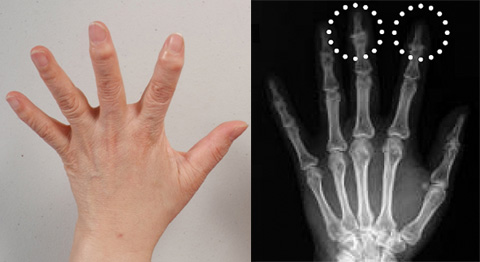

손가락 퇴행성관절염은 손가락 관절의 연골이 점차 마모되면서 발생하는 만성 질환이에요. 특히 나이가 들면서 발생할 확률이 높아지지만, 반복적인 손가락 사용이나 부상으로 인해 젊은 사람들에게도 나타날 수 있답니다. 통증, 뻣뻣함, 부종이 주요 증상이며, 움직일 때 "뚝뚝" 소리가 날 수도 있어요.

- 관절 변형 (심한 경우)